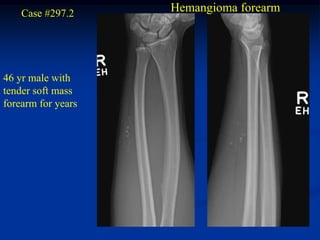

Case #297.2     Hemangioma forearm

46 yr male with

tender soft mass

forearm for years

Cor T-1   T-2   Gad

Sag T-1   T-2   Gad

Axial T-1         T-2

Gad

Case #297.2 Hemangioma forearm 46 yr male with tender soft mass forearm for years

• 310.

• 311.

• 312.

Axial T-1 T-2 Gad

• 313.